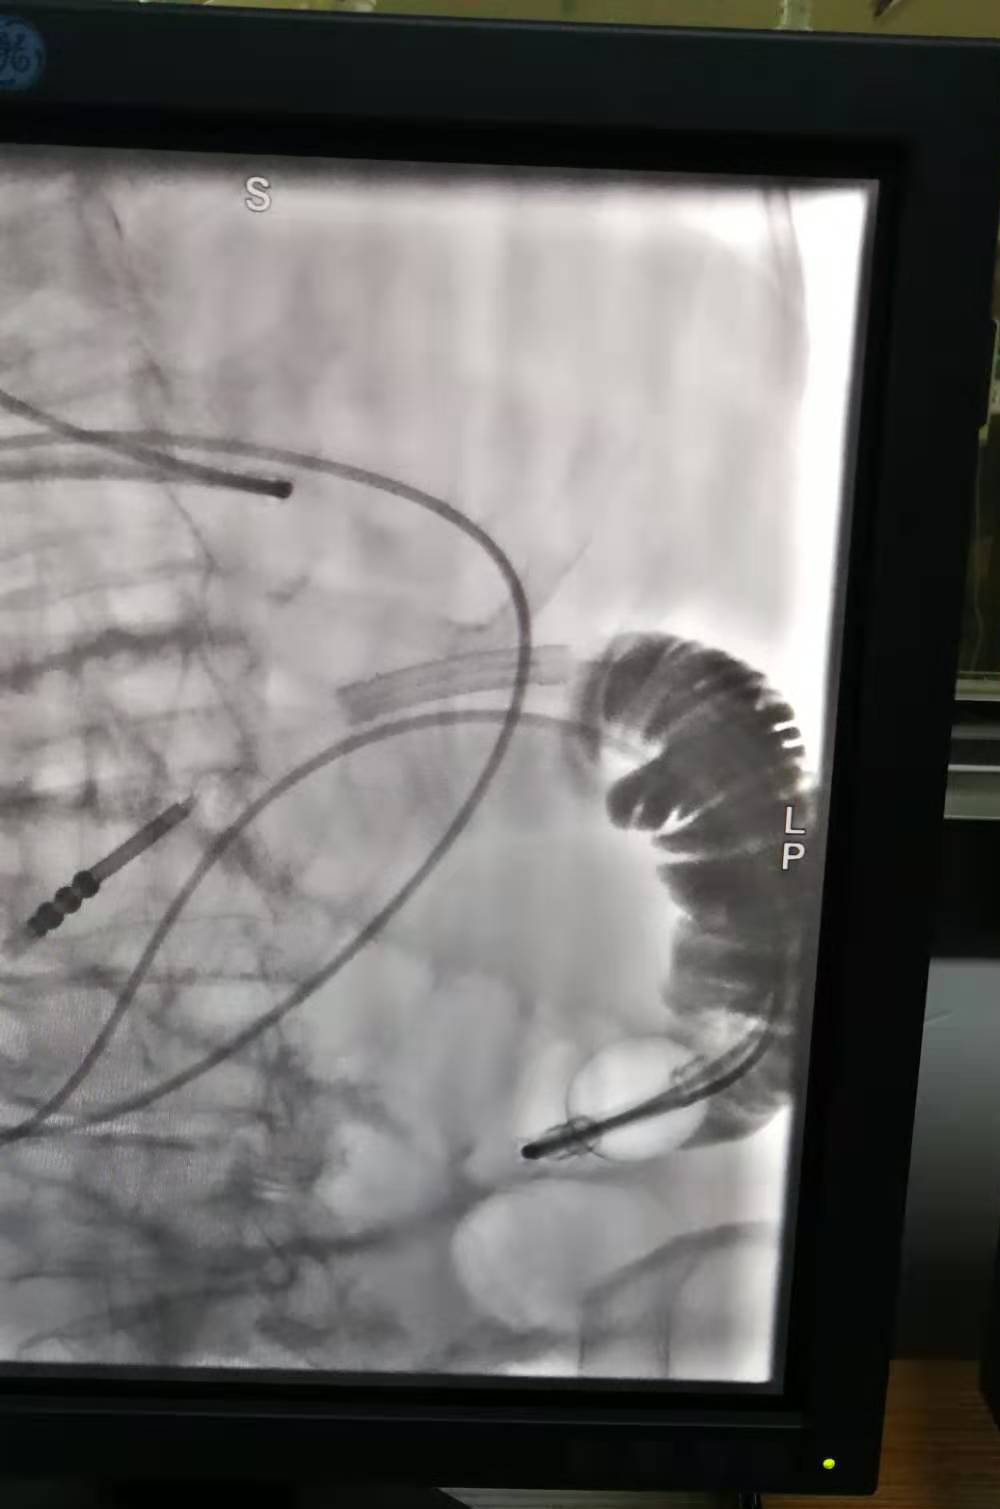

2020年11月9日,菏澤醫(yī)專附屬醫(yī)院消化科專家劉慶民、介入中心專家趙金旭及ICU工作人員為一名96歲嚴(yán)重腸梗阻患者成功放置經(jīng)鼻留置腸梗阻導(dǎo)管,標(biāo)志著菏澤醫(yī)專附屬醫(yī)院在消化科介入治療方面邁入了新的篇章。

因病情比較危重,腸梗阻時(shí)間較長,心肺功能差,為爭(zhēng)取治療時(shí)間,劉慶民、趙金旭及ICU副主任魏斌、介入科等人員于11月9日夜間加班為老人進(jìn)行介入下置管,手術(shù)成功完成,為病人贏得了寶貴的治療時(shí)間。置管后引流良好,腹脹明顯好轉(zhuǎn),第二天透視,液氣平消失,梗阻解除。